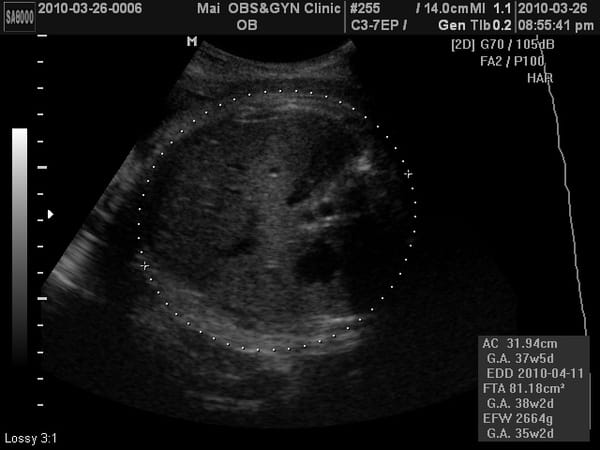

小老虎第九次產檢,驗尿ok,血壓………,母親體重65.9KG,兩周共增重1.2KG。

小老虎上次產檢2500公克,這次2600多公克,這兩周吃的東西都長在媽媽身上。

這次又看得到4D照了,相當有肉,臉頰有肉、鼻子有肉、嘴巴也很有肉、連胸部也擠出一團肉~~~

我一直說可能是因為頭在下被擠壓的關係,所以看起來很有肉啦~不過M醫生卻沒有回我話。

M醫生關心的頭小議題,本周測量頭的大小:8.67cm

如果是8.1cm就有小腦的可能性。

醫生說:頭骨測量是點對點,不像身體是用概括計算的,所以不會有落差,看起來是沒有小腦症的疑慮。